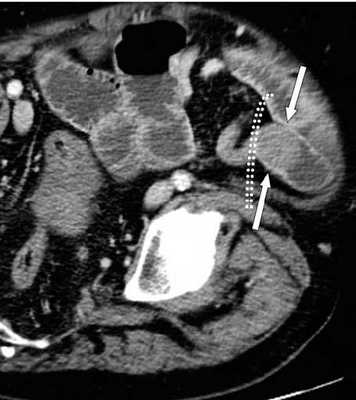

(а) При КТ с контрастированием в аксиальной проекции выявлена транспозиция верхней брыжеечной артерии (указатель) и вены (стрелка).

(б, в) На более низких уровнях при КТ в аксиальной проекции выявлен симптом «водоворота» (стрелка), представляющий собой перекручивание верхней брыжеечной вены и ее ветвей, брыжеечного жира и петель кишки вокруг верхней брыжеечной артерии по часовой стрелке.

Ультрасонография (УС) информативна при патологическом перекручивании верхних брыжеечных артерии и вены (симптом «водоворота»), выявляемом при цветном допплеровском картировании. Однако зависимость от мастерства исследователя, а также газ в тонкой кишке, мешающий исследованию верхних брыжеечных сосудов, часто ограничивают диагностическую пользу. КТ стала важным методом визуализационной диагностики, особенно при завороте тонкой кишки у взрослых. Как и при УС, характерным признаком при КТ служит симптом «водоворота», который возникает в результате перекручивания верхней брыжеечной вены и ее ветвей, брыжеечного жира, кишки и ветвей верхней брыжеечной артерии вокруг самой верхней брыжеечной артерии, чаще по часовой стрелке.